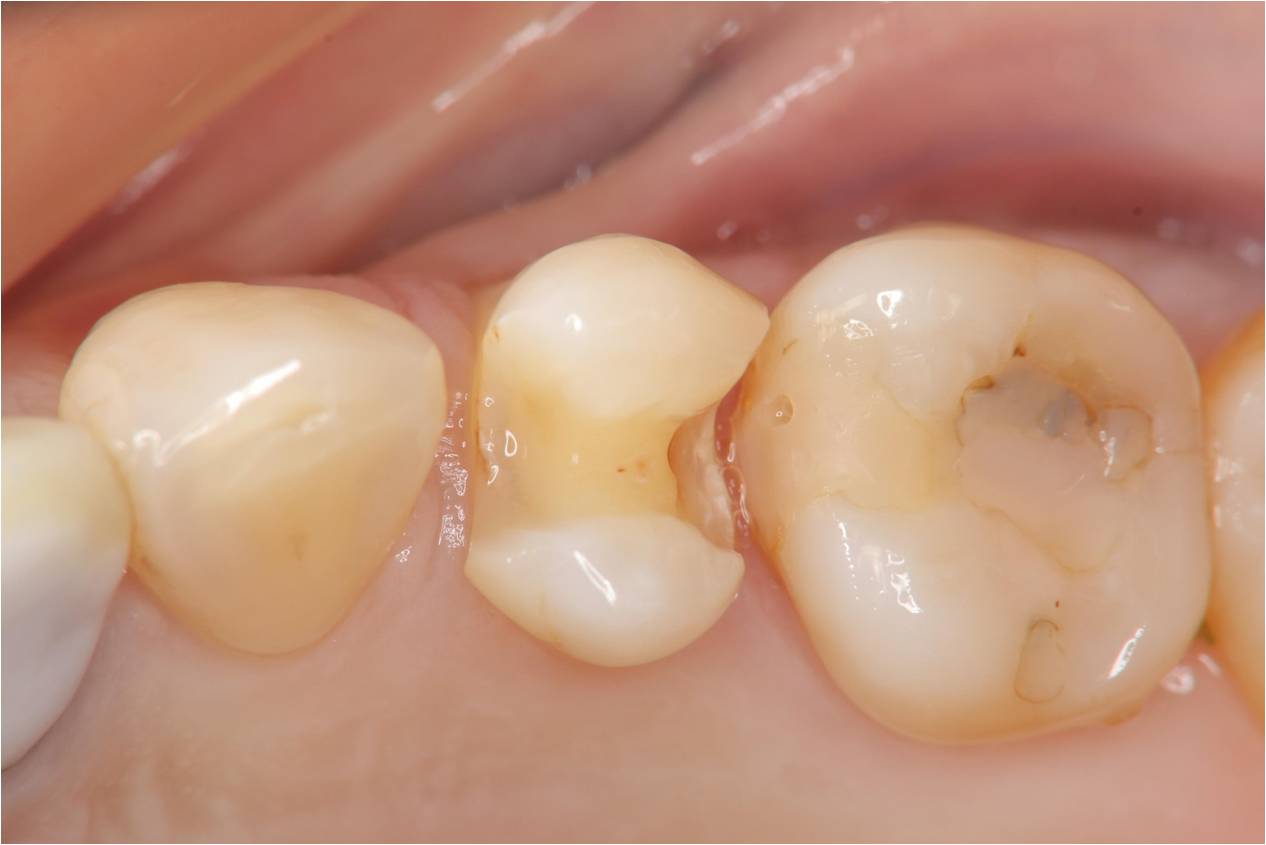

崁體窩洞製備